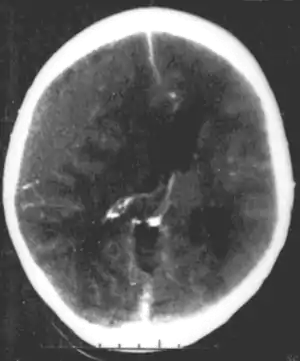

A number of infectious diseases can be transmitted congenitally (either before or at birth), and can cause serious neurodevelopmental problems, as for example the viruses HSV, CMV, rubella (congenital rubella syndrome), Zika virus, or bacteria like Treponema pallidum in congenital syphilis, which may progress to neurosyphilis if it remains untreated. Protozoa like Plasmodium[17] or Toxoplasma which can cause congenital toxoplasmosis with multiple cysts in the brain and other organs, leading to a variety of neurological deficits.